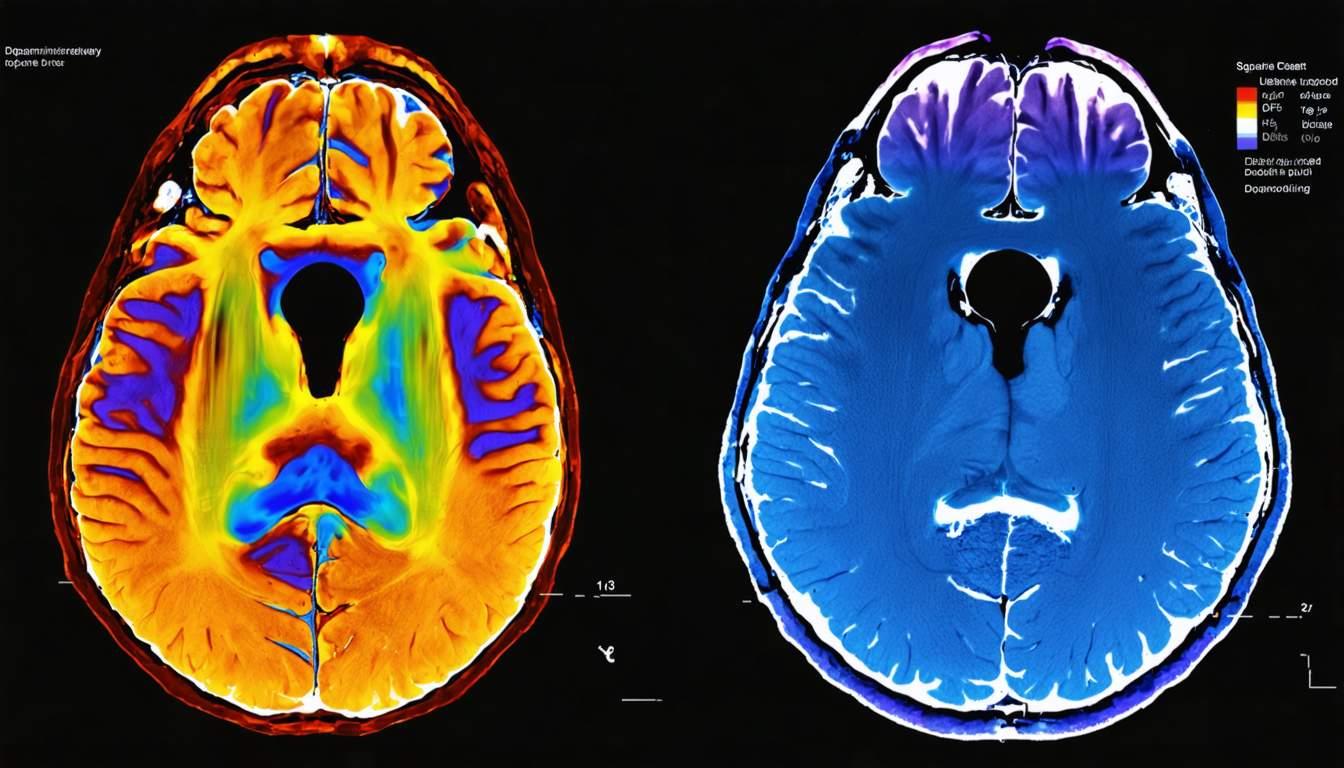

Positron Emission Tomography (PET) and Single Photon Emission Computed Tomography (SPECT) are valuable neuroimaging techniques used to assess dopaminergic dysfunction in movement disorders such as Parkinson’s disease. These modalities allow for detailed visualization of dopamine transporter (DAT) activity, helping clinicians differentiate between various movement disorders.

PET imaging utilizes radiotracers such as fluorodopa (18F-DOPA) to evaluate presynaptic dopamine synthesis and dopamine receptor binding. This imaging method provides high sensitivity in detecting early Parkinsonian changes.

SPECT imaging commonly employs radiotracers such as Ioflupane (123I-FP-CIT) to assess DAT activity. It aids in distinguishing essential tremor from Parkinsonian syndromes, making it a valuable diagnostic tool.